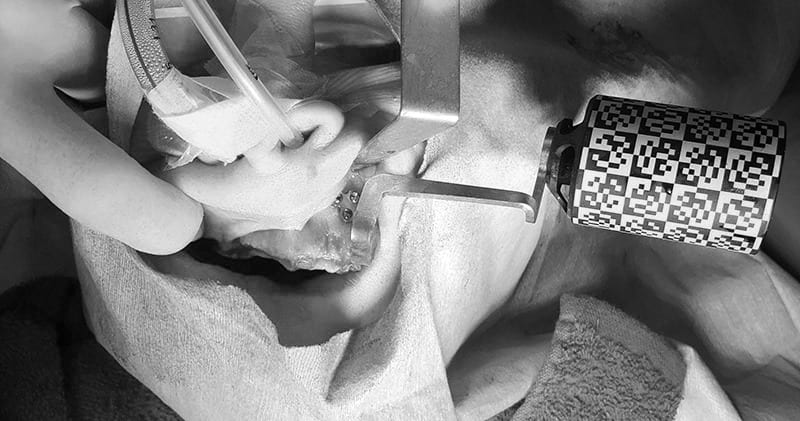

手術

X-Guideを使用し安全で正確なインプラント手術を行なっております

upper jaw

術前の治療計画通りの位置に、インプラントを埋入する事が出来ました。

このように、ボーンリダクションを伴う、抜歯即時荷重症例において、Xガイドを用いることで、非常にシンプルな手術が行え、従来法(サージカルガイド)より正確な手術を行う事が可能となります。